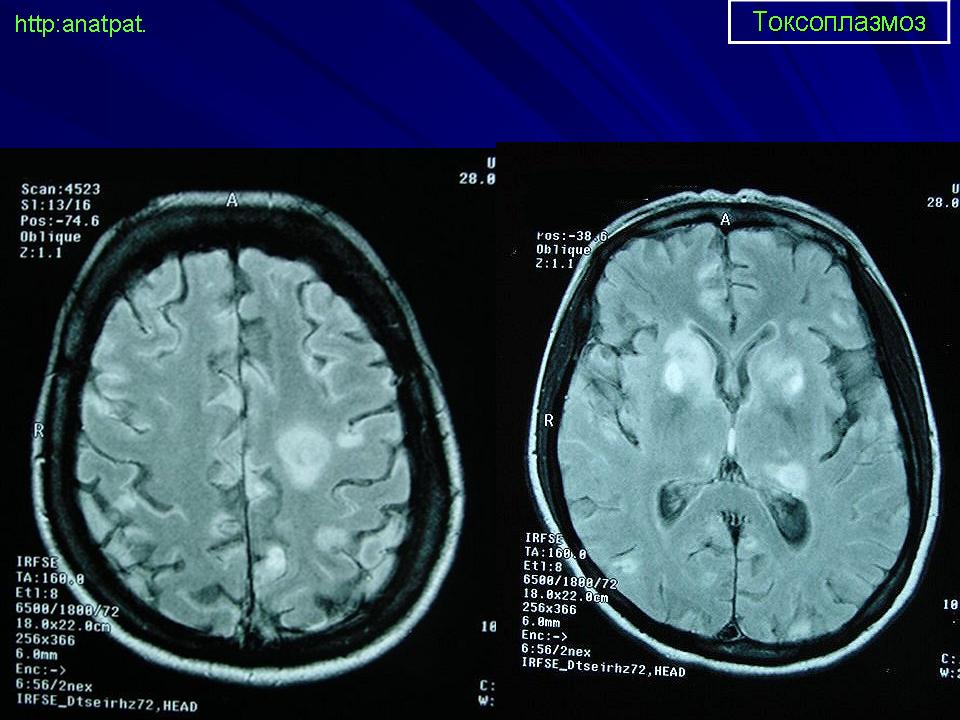

Пато морфологи я. Патоморфологические изменения при приобретенном токсоплазмозе изучены в экспериментах на животных. Установлено, что в центральной нервной системе развиваются явления некротического перивентрикулита, мелкие очаги некроза в субкортикальном белом веществе. В сосудах головного мозга, мягкой мозговой оболочки и хориоидальных сплетениях отмечаются признаки серозно-пролиферативного воспаления. Обнаруживаются также глазные патологоанатомические изменения (типа ретинита, хориоидита, иридоциклита) и изменения во внутренних органах (сердце, легкие, печень, селезенка).

Врожденный токсоплазмоз чаще, чем приобретенный, приводит к летальному исходу. В головном мозге умерших обнаруживаются более или менее значительные очаги обызвествления, участки размягчения мозгового вещества, полости, заполненные жидкостью. Как правило, отмечается гидроцефалия, обусловленная воспалительной и рубцовой облитерацией водопровода среднего мозга, отверстий Люшка или других участков ликворных путей. Истон-чение вещества полушарий мозга может достигать степени их полного исчезновения.

Особенно характерна триада симптомов: хореоретинит, гидроцефалия, очаги обызвествления в головном мозге. Кроме того, отмечаются менингеальные знаки, тонические и клонические судороги, парезы, параличи, олигофрения.

Неврологические симптомы могут сочетаться с пневмонией, миокардитом, гепатоспленомегалией, с выраженной желтухой. В спинномозговой жидкости отмечается лимфоцитарный плеоцитоз (до 500 • 106 в 1 л), ксантохромия (“канареечный” ликвор). На рентгенограмме черепа обнаруживаются обызвествления в глубинных отделах головного мозга, сосудистых сплетениях. Как и приобретенный, врожденный токсоплазмоз может протекать остро, подостро и хронически.

Церебральный токсоплазмоз.

Церебральный токсоплазмоз